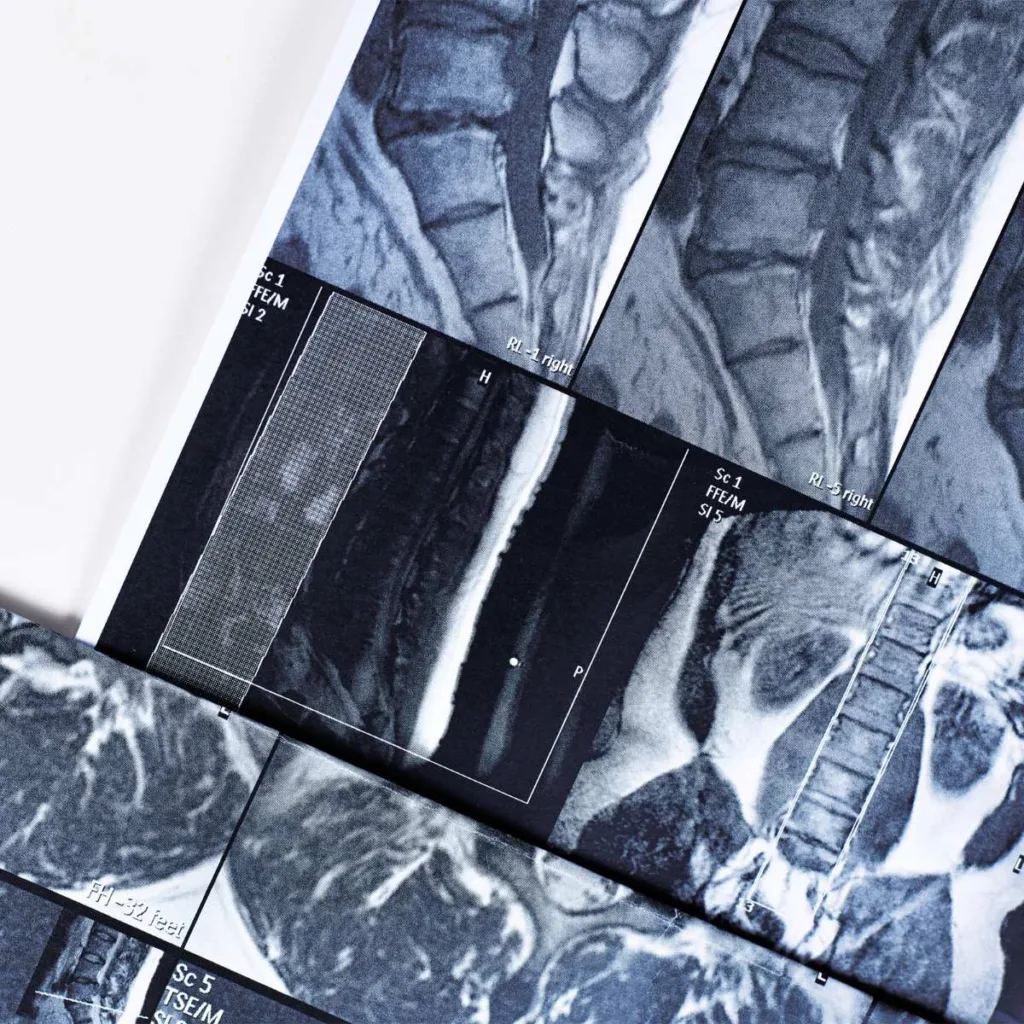

Resonancia Magnética de Columna